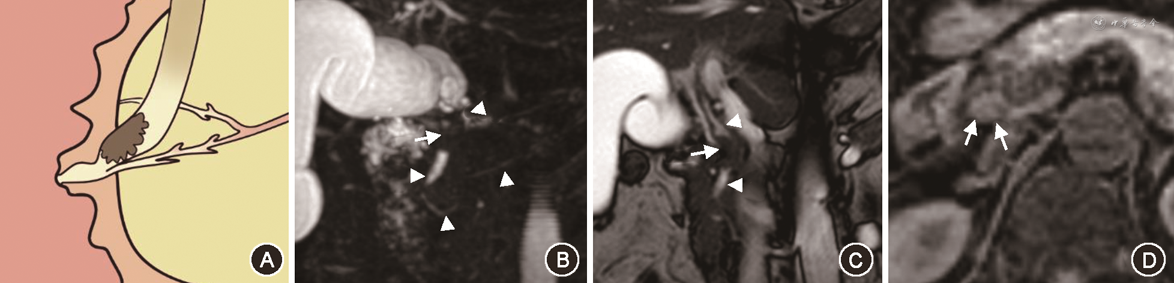

在对有意义单因素指标的分析中,笔者将PAC的MRI征象进行总结,最后归纳为十二指肠乳头结节型、胰腺肿块型、胆总管壁增厚型、壶腹部肿块型及胆总管腔内结节型5种表现类型。十二指肠乳头结节型MRI征象为位于十二指肠腔内的病灶,多为等信号,在十二指肠乳头形成突入腔内的结节,MRCP上胆总管及胰管扩张呈双管征,胰胆管角度较小,双管征走行呈平行或聚拢(图1)。胰腺肿块型MRI征象为胰腺内低信号肿块,MRCP上胆总管及胰管单独或同时狭窄截断可分别出现双管征、三管征、四管征,截断胰管周围可见扩张侧支,肿块引起胰胆管角度增大,管征呈分离走行(图2)。胆总管壁增厚型MRI征象为胆总管远段管壁增厚,近段胆管扩张,MRCP上胰管较少扩张,近段扩张胆管、梗阻下方远段胆总管与胰管呈三管征(图3)。壶腹部肿块型在MRI图像上表现为壶腹部跨壁生长的肿块,可与胰腺、十二指肠肠壁分界不清,但较少使十二指肠乳头表现为结节型,MRCP管征多为双管征(图4)。胆总管腔内结节型在MRCP图像上远端胆总管内见结节样充盈缺损伴胆道梗阻,远段胆总管、近段扩张胆总管及胰管呈三管征(图5)。

Fisher精确概率法结果显示,IPAC与PPAC在MRI影像5分型的差异具有统计学意义(P<0.001)(表4)。经调整检验水准后的 Bonferroni 法两两比较结果显示,十二指肠乳头结节型与胰腺肿块型、胆总管壁增厚型及壶腹部肿块型的差异均具有统计学意义(均P<0.005)。IPAC多表现为十二指肠乳头结节型(15/21,71.4%)(图1),PPAC更多表现为胰腺肿块型(18/38,47.4%)、胆总管壁增厚型(9/38,23.7%)或壶腹部肿块型(9/38,23.7%)(图2, 3, 4),IPAC(2/21,9.5%)与PPAC(0,0)均较少表现为胆总管腔内结节型(图5)。